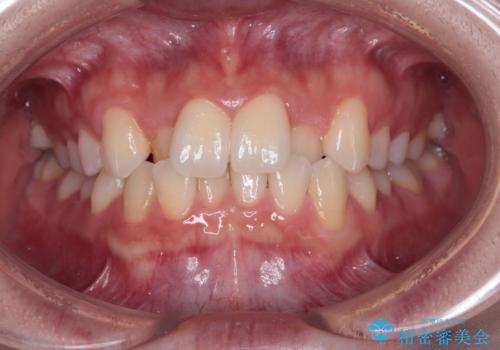

- 八重歯と乳歯が残っていることを気にして来院された患者様です。

乳歯が3歯残っており、下顎は左右ともに後続永久歯がない状態でした。

口元が突出しており、口が閉じにくかったため、乳歯を含め上下5歯を抜歯して矯正治療を行うこととしました。

下顎の乳歯は永久歯と比べて幅が大きいため、抜歯した場合のスペースが大きく、治療には長期間を要することが一般的です。

今回の患者様は中学生ということもあり、成人の患者様と比べ動きが速く、2年間で治療を終えることができました。